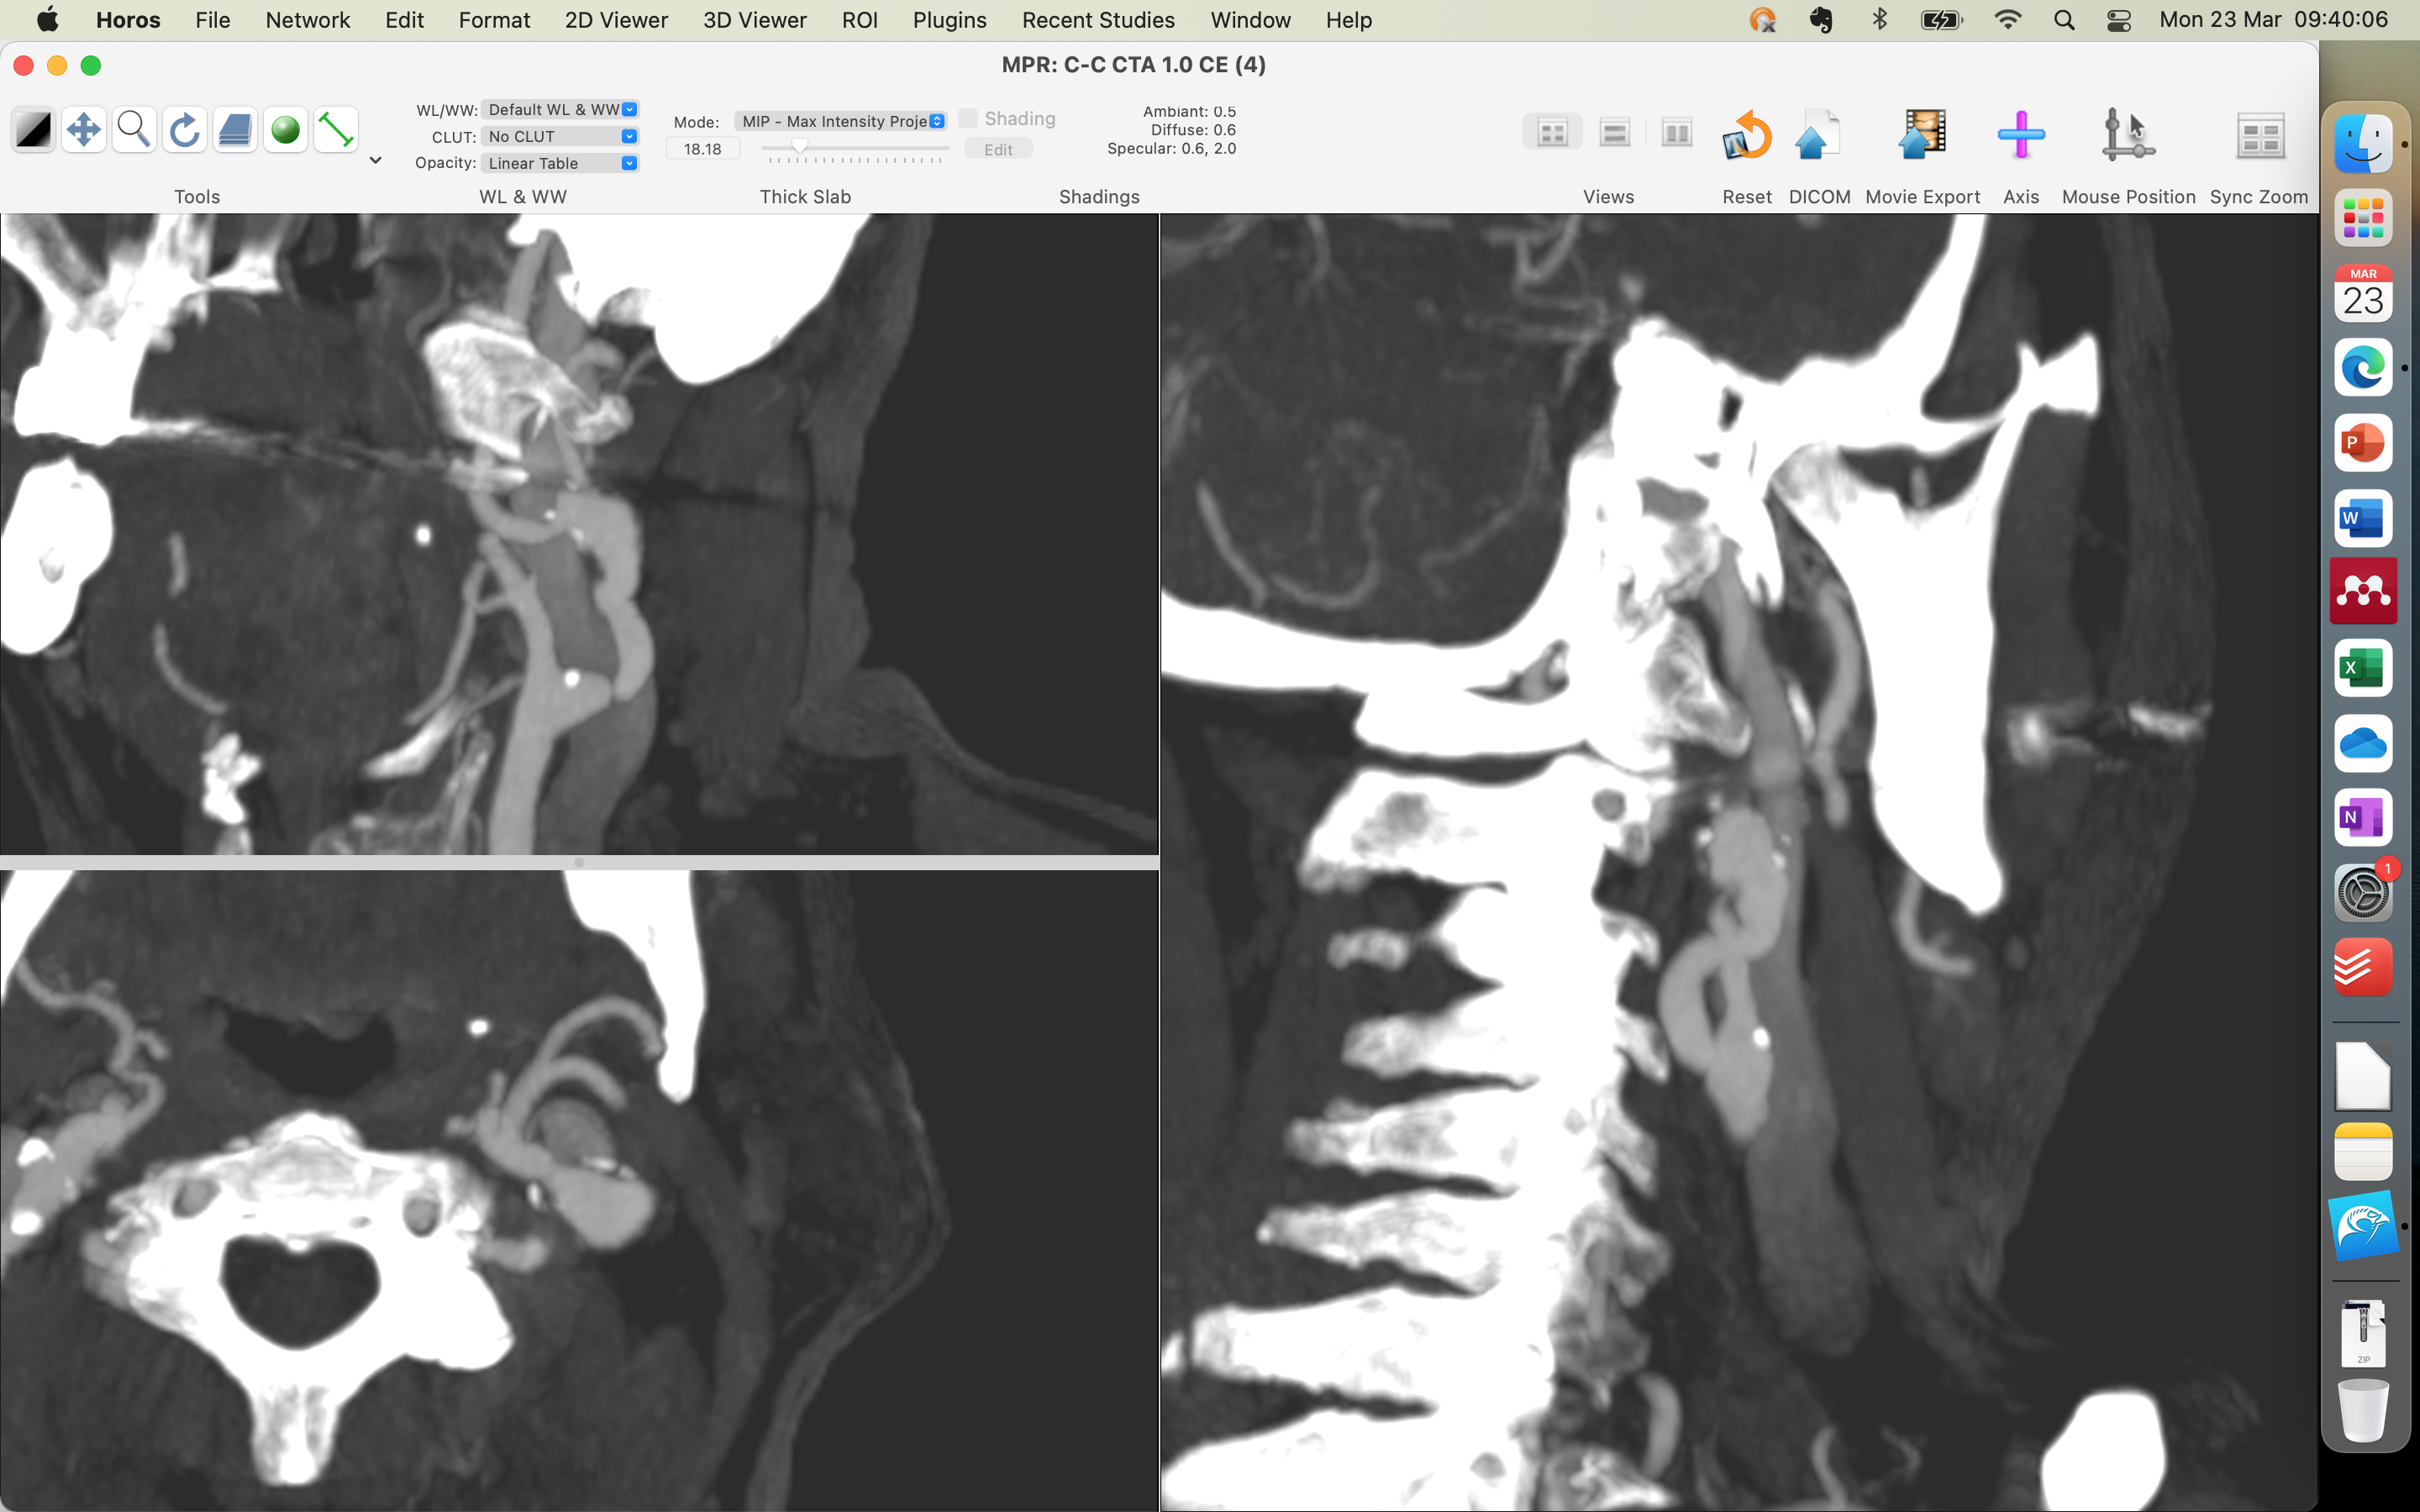

-ANGIOTOMGRAFIA ARTERIALDO CRÂNIO(04/11/2025): PLACAS ATEROMATOSAS PREDOMINANTEMENTE CALCIFICADAS NOS SEGMENTOS INTRACRANIANOS DAS ARTÉRIAS CARÓTIDAS INTERNAS, SEM PROMOVER ESTENOSE. ARTÉRIAS CEREBRAIS ANTERIORES, MÉDIAS E POSTERIORES SEM SINAL DE OCLUSÃO OU ESTENOSE. SEM EVIDÊNCIAS DE MAL FORMAÇÃO ARTERIO-VENOSA OU DILATAÇÕES ANEURISMÁTICAS. IMPRESSÃO DIAGNÓSTICA NO LAUDO: ATEROMATOSE CAROTÍDEA , SEM DETERMINAR ESTENOSES RELEVANTES.

-ANGIO TC ARTERIAL CERVICAL(04/11/2025): IMPRESÃO DX: DOENÇA ATEROMATOSA COM IRREGIULARIDADES/ULCERAÇÕES SUPERFICIAIS NO ARCO AÓRTICO E PRINCIPAIS TRONCOS ARTERIAIS SUPRA-AÓTICOS, SEM ESTENOSE; DOENÇA ATEROMATOSA MISTA NA BIFUCAÇÃO CAROTÍDEA COM IRREGULARIDADES SUPERFICIAIS : CARÓTIDA INTERNA DIREITA: ESTENOSE LEVE(INFERIOR A 50%, CARÓTIDA INTERNA ESQUERDA : ESTENOSE IMPORTANTE NA PORÇÃO PROXIMAL( ACIMA DE 70%). SEGMENTO DE ECTASISA FOCAL NO TERÇO MÉDIO DA CARÓTIDA INTERNA ESQUERDA COM SINAIS DE ACOMETIMENTO´POR DOENÇA ATEROMATOSA.

-DOPPLER DE ARTÉRIAS CAROTÍDEAS E VERTEBRAIS( 22/09/2025): EXTENSA ATEROMATOSE CAROTÍDEA , DESTACANDO AREA DE KINGING NA EMERG~ENCIA DA CARÓTIDA INTERNA ESQUERDA QUE ASSOCIADA A PLACA FIBROCALCIFICADA DETERMINAM ESTENOSE MAIOR QUE 70%.

ESTENOSE DE 90% DE ACIE ASSINTOMATICO, ATEROSCLOSE/FIBRODISPLASIA (ESTENOSE DISTAL AO OSTIO COM DILATACAO DISTAL)

ESTENOSE ACID 60% ASSINTOMATICO

- ENCAMINHO O PACIENTE PARA SANTA CASA DE MARILIA PARA REALIZAR ARTERIOGRAFIA DE CAROTIDAS E VERTEBRAIS PARA DEFINIR SE IRA OU NAO REALIZAR ANGIOPLASTIA/ ENDARECTOMIA,